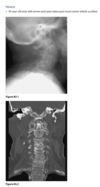

An anteroposterior radiograph was obtained for an 81-year-old man who fell. He entered the

emergency room with his arm locked in an abducted position high above his head.

The right humeral head is dislocated infe-

riorly at the glenohumeral joint. The superior aspect

of the humeral head does not contact the inferior

aspect of the glenoid rim, and the arm is held over

the patient’s head in a fixed position.

Luxatio erecta

With luxatio erecta, the inferior joint capsule is

almost always torn. There may also be associated fractures of the greater tuberosity, acromion, clav-

icle, coracoid process, and glenoid. The most seri-

ous complications are injuries to the brachial plexus

and axillary artery.